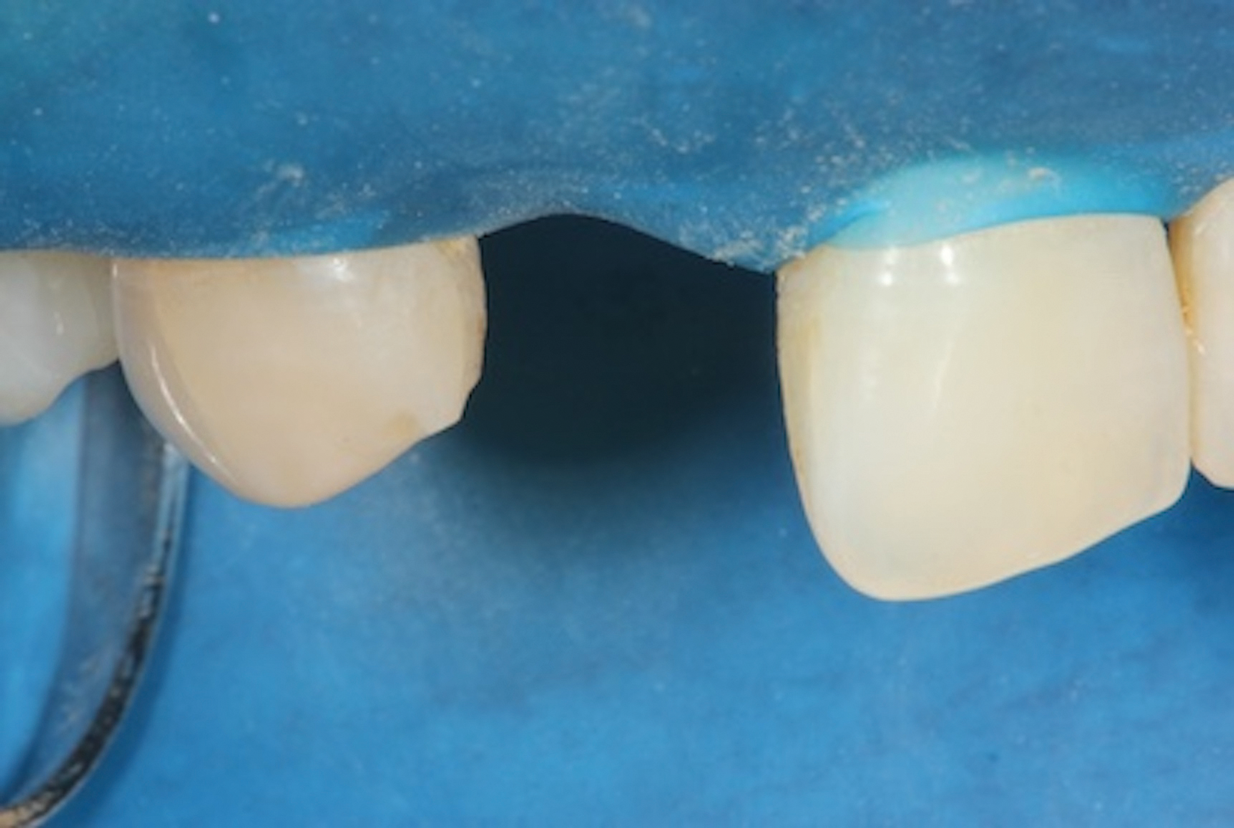

1. Isolate the Operating Field

For any adhesive procedure, optimizing bond strength hinges on achieving proper isolation of the operating field. Placing a rubber dam ensures a pristine and fluid-free field, creating an ideal environment for both bonding and the subsequent development of the resin bridge (Figure 3). Achieving complete isolation is particularly important in cases involving replacement of a missing tooth immediately after extraction or implant placement.

(3.) Placement of a rubber dam to achieve isolation.

Figure 3